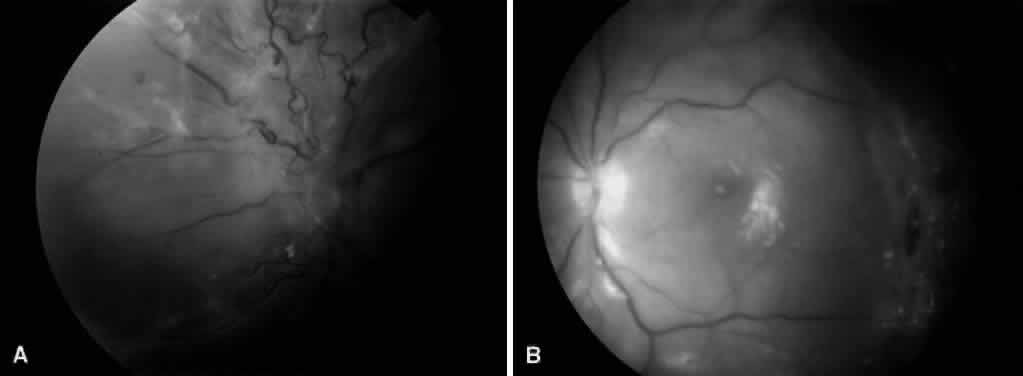

Vitreous traction and contraction of proliferative tissue can produce retinal tears, leading to combined traction-rhegmatogenous detachments. Unlike purely tractional detachments, extramacular rhegmatogenous detachments frequently progress to involve the macula, leading to rapid and severe visual loss. Thus, surgical repair is indicated in combined detachments, whether or not the macula is involved. Often, the retinal breaks are located posterior to the equator, adjacent to areas of fibrovascular proliferation that are under severe vitreoretinal traction. Therefore, this condition is difficult to treat by conventional scleral buckling methods, whereas vitrectomy (with or without scleral buckling) is effective in treating this condition (Fig. 5). Intraocular long-acting gas tamponade is required to treat these detachments. Combined traction-rhegmatogenous detachments have a lower success rate than pure tractional detachments or nonclearing vitreous hemorrhage. In an analysis of 172 eyes that underwent vitrectomy for combined traction-rhegmatogenous diabetic retinal detachment, 48% had an improved visual acuity on final examination.21 A final visual acuity of 20/100 or better was achieved in only 25% of eyes, and a final visual acuity of 5/200 was achieved in 56%. Visual loss progressed to no light perception in 23% (compared with 19% for macular traction detachment and 6% for nonclearing vitreous hemorrhage). Preoperative factors associated with a favorable visual prognosis included visual acuity of 5/200 or better, absence of iris neovascularization, and absence of retinal detachment involving the macula. The only intraoperative factor found to be associated with a favorable visual prognosis was the absence of iatrogenic retinal breaks.

Fig. 5. A. Preoperative fundus photograph of an eye with combined traction-rhegmatogenous retinal detachment from severe proliferative diabetic retinopathy. B. Postoperative fundus photograph of the same eye after vitrectomy, membrane dissection (using delamination technique), and endolaser photocoagulation.